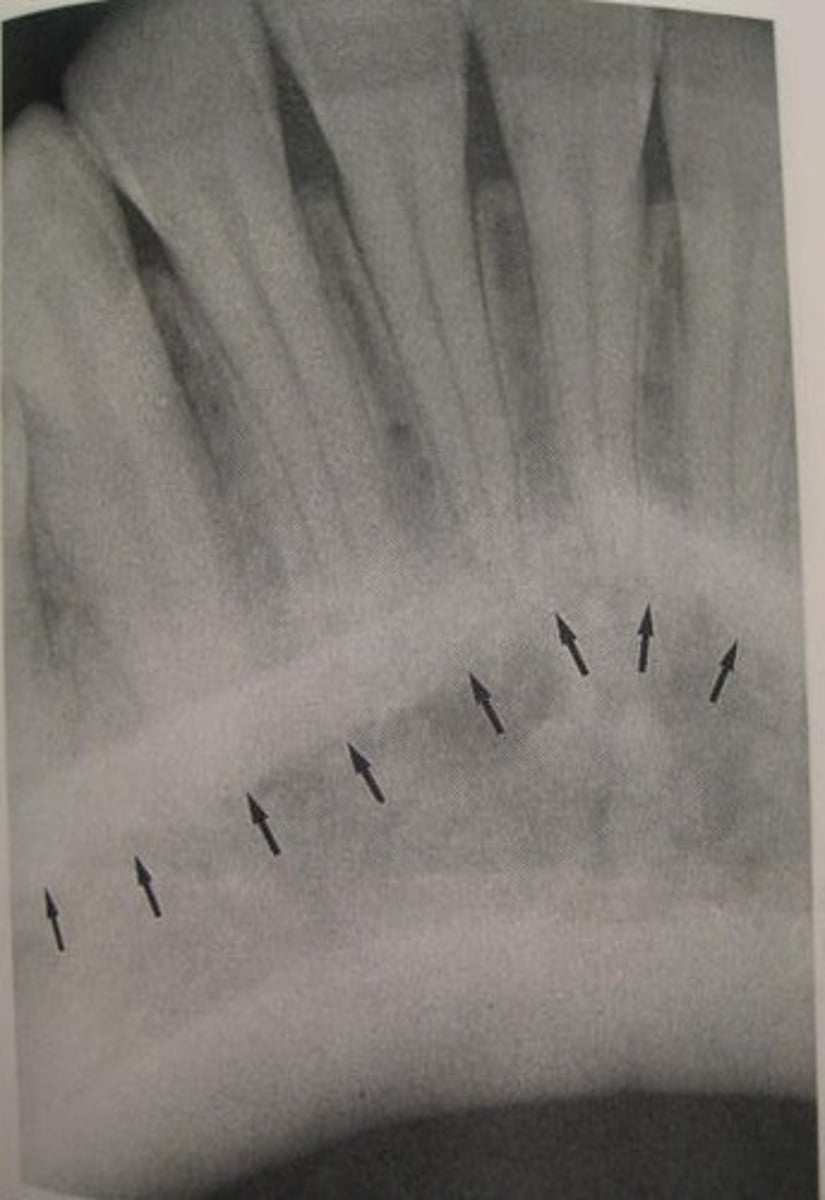

what is this?

what is this radiolucent area in the image?